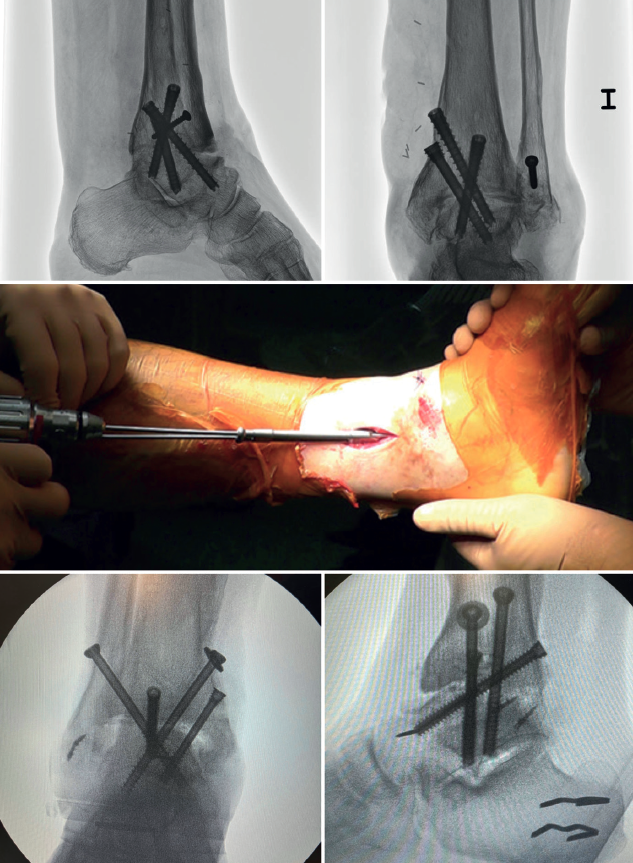

In arthroscopic ankle arthrodesis, the use of percutaneously placed compression screws is the technique of choice (Figure 5).

Most authors consider the use of cannulated screws (3 to 4) to be the ideal fixation method. The diameters of the chosen screws should be between 6 and 7 mm. This technique achieves 85-100% fusion and 84-95% patient satisfaction rates(19).

Van Dijk, Kerkhoffs et al.(20) reported excellent results with the use of three screws as the standardized method for ankle arthrodesis.

Screw configuration and placement

Depending on the deformity involved and according to preoperative planning, screw placement is carried out starting with the compression screw that counteracts the deformity.

In other words, in arthropathies with a varus component, we would start with a lateral screw, while in valgus misalignments the recommendation is to place the first screw from the medial side. The second screw should be on the side opposite to the first. Both should provide adequate compression between the joint surfaces(17).

In general, a minimum of three screws are used. The third screw is the so-called home run screw, the importance of which has been highlighted by Holt et al.(21). It is directed across the ankle from the posterior part of the tibia to the neck of the talus. A fourth screw may be used as an augmentation of the first, counteracting the main deformity.

Goetzmann et al.(22), in their review of 111 cases, supported the use of at least three screws for fixation of arthroscopic tibiotalar arthrodesis. The addition of a third screw appears to be associated with a lower risk of pseudarthrosis and shorter consolidation time. These effects can be attributed to an increased stability of the construct.

Glick, Myerson(23)et al. reported that the configuration conferring the greatest rigidity to the osteosynthesis comprises two screws from medial and one from the lateral side.